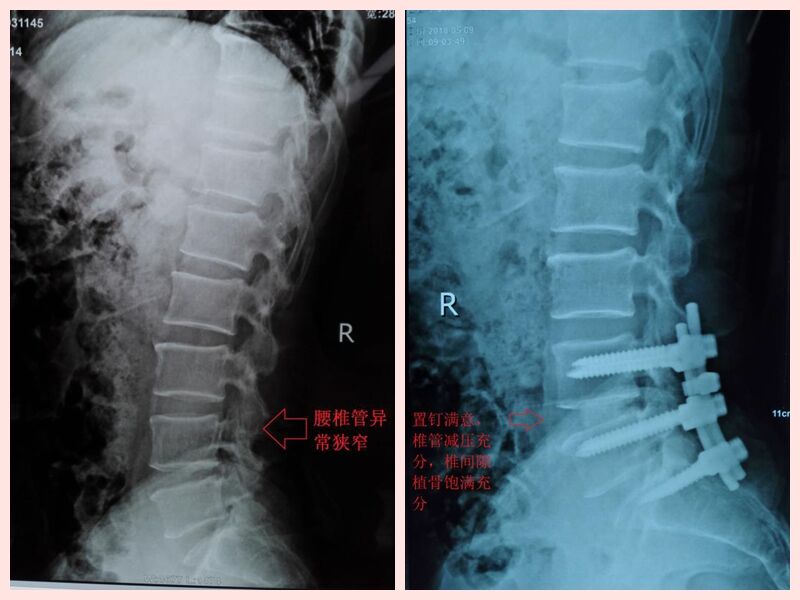

经多方打听,娄底市骨伤医院在治疗腰腿疼痛方面有独特疗效,特别是脊柱微创手术有立竿见影之功效,故于4月13日在家人的搀扶下来前往骨伤医院就诊。在门诊经过仔细的体查及阅片后收入住院,第二天,科主任谢军副主任医师邀请骨科专家刘卓华院长会诊,经全科会诊大讨论后,认为该患者目前诊断为“腰椎管狭窄症、 腰椎间盘突出症术后”。因患者既往22年前有腰椎间盘手术病史,腰部已有大量瘢痕组织,原有腰部正常解剖变异大,而且目前患者腰椎管狭窄症状明显,神经根性症状突出,脊髓及神经受压范围较广泛,单纯微创椎间孔镜手术通道难以建立,神经固有压迫难以解除,脊柱稳定性难以重建,又不适宜做微创手术,综合上述原因,刘院长决定为肖大叔施行后路减压椎体间植骨融合内固定手术。

4月19日在做好充分的术前准备下,患者被推进手术室,由刘卓华院长主刀、科主任谢军副主任医师、付中城主治医师组成的脊柱手术团队,经过4个小时的手术,小心分离严重瘢痕增生的腰背部软组织,因术中脊髓硬膜囊已经和软组织粘连在一起,稍有不慎就会撕破硬膜囊,引起脑脊液漏及神经症状甚至瘫痪,刘院长凭借自己多年的手术经验及精湛技术,一点点将神经根及硬膜囊分开解压,同时植钉、摘除椎间盘,椎间隙植骨融合,术中透视满意后仔细缝合,患者手术经过顺利,手术成功。术后患者即右下肢疼痛症状消失,右下肢直腿抬高试验阴性,患者当天晚上就睡了一个好觉,第二天查房时向我们医务人员竖起大拇指,病房里时不时传出他爽朗的笑声。